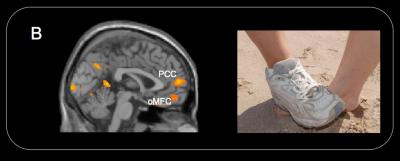

The scans showed that the parts of the brain activated when adults see pain were also triggered in children.

"Consistent with previous functional MRI studies of pain empathy with adults, the perception of other people in pain in children was associated with increased hemodymamic activity in the neural circuits involved in the processing of first-hand experience of pain, including the insula, somatosensory cortex, anterior midcigulate cortex, periaqueductal gray and supplementary motor area," Decety wrote.

However, when the children saw animations of someone intentionally hurt, the regions of the brain engaged in social interaction and moral reasoning (the temporo-parietal junction, the paracigulate, orital medial frontal cortices and amygdala) also were activated.